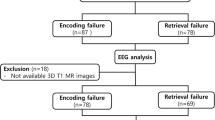

The sample consisted of 379 individuals divided into 118 MCI (aged from 58 to 87) and 261 CI participants (aged from 41 to 82). The participants were recruited from the Hospital Universitario San Carlos [17] and from “Centro para Mayores del Distrito de Chamartín”, both located in Madrid (Spain). General inclusion criteria were as follows: a modified Hachinski score ≤ 4, a Geriatric Depression Scale (short form) score ≤ 5, and T1, T2, and diffusion-weighted MRIs within 54 weeks before the MEG recordings (on average, the time period between the MEG and MRI recordings was 3 months) without an indication of infection, infarction, or focal lesions (rated by two independent experienced radiologists [18]). In addition, the criteria for the MCI diagnosis were established according to the NIA-AA clinical criteria [19]. For more information about the diagnostic criteria for MCI, see López et al. [20]. For CI participants, we exclude subjects with evidence of significant hippocampal atrophy in a T1-weighted MRI scan within 2 months before MEG acquisition, as hippocampal atrophy is considered a brain marker associated with neurodegeneration [21]. No one of the participants exhibited a history of psychiatric or neurological disorders other than MCI. Furthermore, we advised subjects to avoid medications that could affect MEG activity, such as benzodiazepines, for 48 h before recordings (A detailed list of the sample characteristics can be found in Table 1).

Genomic DNA was extracted from 10 ml blood samples in ethylenediaminetetraacetic acid. Detection of APOE genotype was performed with TaqMan technology using an Applied Biosystems 7900 HT Fast Real-Time PCR machine (Applied Biosystems, Foster City, CA). See the genotyping method previously described in Cuesta et al. [32] for more information. All the sample was included independently of APOE genotype in the initial analysis. Then, to evaluate the potential moderation role of genotype, the participants were classified as APOE ɛ4 carriers and noncarriers (i.e., ɛ3ɛ3). Participants who presented less frequent allele combinations (i.e., ɛ2ɛ2, ɛ2ɛ3, ɛ2ɛ4, and ɛ4ɛ3ɛ4) were excluded from the sample.